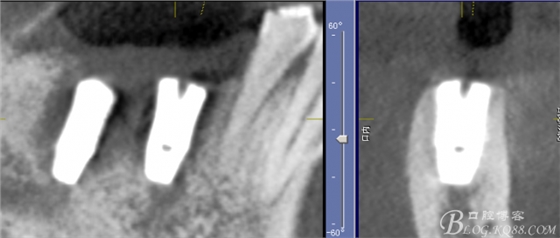

CT可見根管內(nèi)有白色顯影物和根周較大暗影

從根管影像看治療還是不錯的,

懷疑牙根微裂,

所以建議患者手術(shù)探查

三維檢查種植體位置,方向,平行度